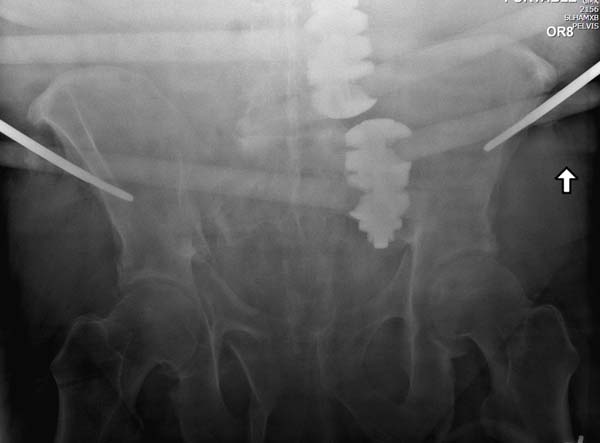

Большое спасибо всем Вам за помощь! Вчера прооперировали пациентку. Выполнили закрытую репозицию левой половины таза на тракционном столе под контролем ЭОП, закрытая фиксация левого КПС двумя каннулированными винтами. Учитывая удовлетворительное стояние отломков лонной и седалищной костей справа, а так же удовлетворительную ширину лона передние отделы стабилизировали системой ЦИТО

Послеоперационные КТ прилагаются

Винты введены в S1

Система ЦИТО это аппарат внешней фиксации, в крылья подвздошных костей вводятся по 2 стержня, которые жестко фиксируются в резьбовой поперечной планке. Есть возможность работать в аппарате с передним отделом таза (компрессия, дистракция).

Планируем оставить эту систему сроком на 4 недели с момента операции.

Описание системы ЦИТО не нашел, но по представленному снимку, здесь точка введения стержня выбрана верхне-передная ость, т.е. место прикрепления m. sartorius. Такая система разработана для ургентной стабилизации таза, и при отстутствии рентгена в приемной. Система не для длительного пользования, и после стабилизации больного должна пройти ревизию со сменой на более стабильный наружный фиксатор, или удалена после окончательной фиксации таза.

В крыле подвздошной кости толщина кости не более 3 мм, и 5 мм стержен в большинстве случаев попадает в никуда, "airball". Со временем стержни расшатываются? и нестабильность не даст “работать в аппарате в передним отделе (компрессия, дистракция)”. Действующие векторы сил создают компрессию спереди, а задние отделы остаются под дистракцией!